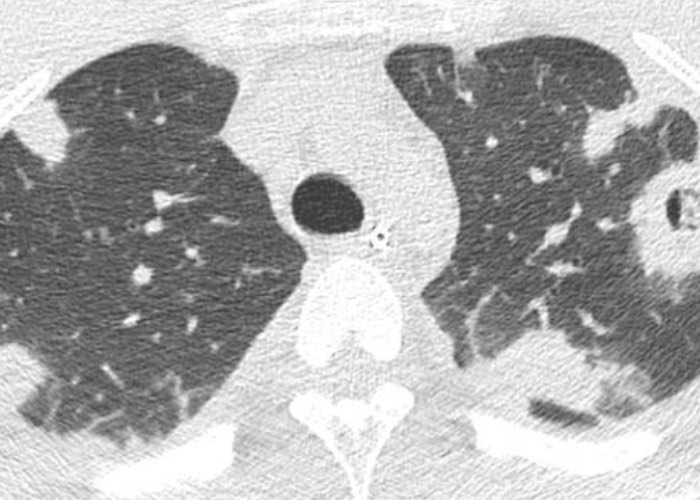

| embolies septiques | condensations nodulaires ±excavées (staph, pyo, candida, BK, Lemierre) |  |

- pneumatocèle = staph et pneumocystose > E. coli, pneumocoque